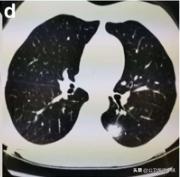

肺部感染涉及多个肺叶-1

肺部感染涉及多个肺叶-2

肺部感染涉及多个肺叶-3

当涉及到一个或多个肺叶,肺功能的影响并不严重时,呼吸急促和呼吸困难的症状也并不严重。随着病情的发展,肺部实变开始吸收,密度降低逐渐变成毛玻璃样的混浊,像融化的糖。